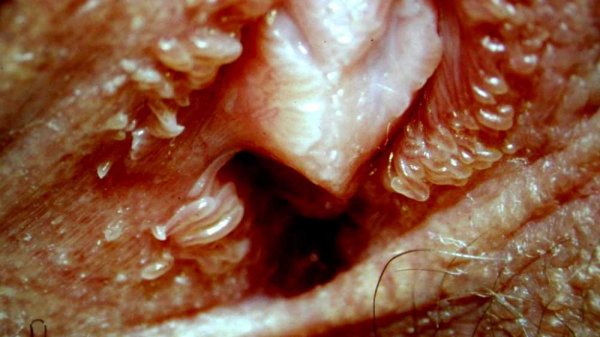

پاپول مرواریدی به صورت برجستگیهای کوچک و گرد دیده میشود که اغلب به رنگ سفید یا همرنگ پوست هستند. اندازه این ضایعات معمولاً کمتر از ۲ میلیمتر است و به شکل منظم در اطراف لبههای داخلی لبهای کوچک یا ناحیه وستیبول (دهلیز واژن) قرار میگیرند. برخلاف زگیل تناسلی، پاپولهای مرواریدی سطحی صاف و براق دارند و بدون التهاب یا ترشح هستند.

پاپول مرواریدی زنانه، برجستگیهای بسیار کوچک، گرد یا نیمکرهای، با رنگ سفید، کرم یا شفاف هستند که در ناحیه تناسلی بانوان مشاهده میشوند. این ضایعات خوشخیم، غیرعفونی و بدون علائم التهابی هستند و معمولاً هیچگونه درد، خارش یا ترشحی ایجاد نمیکنند. برخلاف زگیل تناسلی یا ضایعات ناشی از عفونت، پاپول مرواریدی یک تغییر طبیعی و فیزیولوژیک پوست به حساب میآید و خطری برای سلامت فرد ندارد.

ماهیت پاپول مرواریدی زنانه

پاپول مرواریدی زنانه به صورت برجستگیهای کوچک، نرم و همرنگ پوست یا کمی سفید دیده میشود. این ضایعات معمولاً بدون درد، خارش یا خونریزی هستند و بیشتر در جوانان و زنان قبل از یائسگی مشاهده میشوند. این پاپولها خوشخیم بوده و با بیماریهای مقاربتی یا عفونتهای ویروسی ارتباطی ندارند، بنابراین نگرانی از انتقال بیماری وجود ندارد.

پاپول مرواریدی زنانه ضایعات کوچک، همرنگ پوست یا کمی سفید هستند که اغلب در اطراف دهانه واژن مشاهده میشوند. ویژگیهای اصلی آنها شامل:

برجستگیهای کوچک، صاف یا کمی گرد

بدون درد، خارش یا خونریزی

غیرعفونی و خوشخیم

بدون گسترش یا تغییر سریع شکل

این ضایعات به دلیل ظاهر خوشهای و شبیه مروارید خود، معمولاً نگرانیهای زیبایی ایجاد میکنند، اما هیچ خطری برای سلامت فرد یا شریک جنسی ندارند.